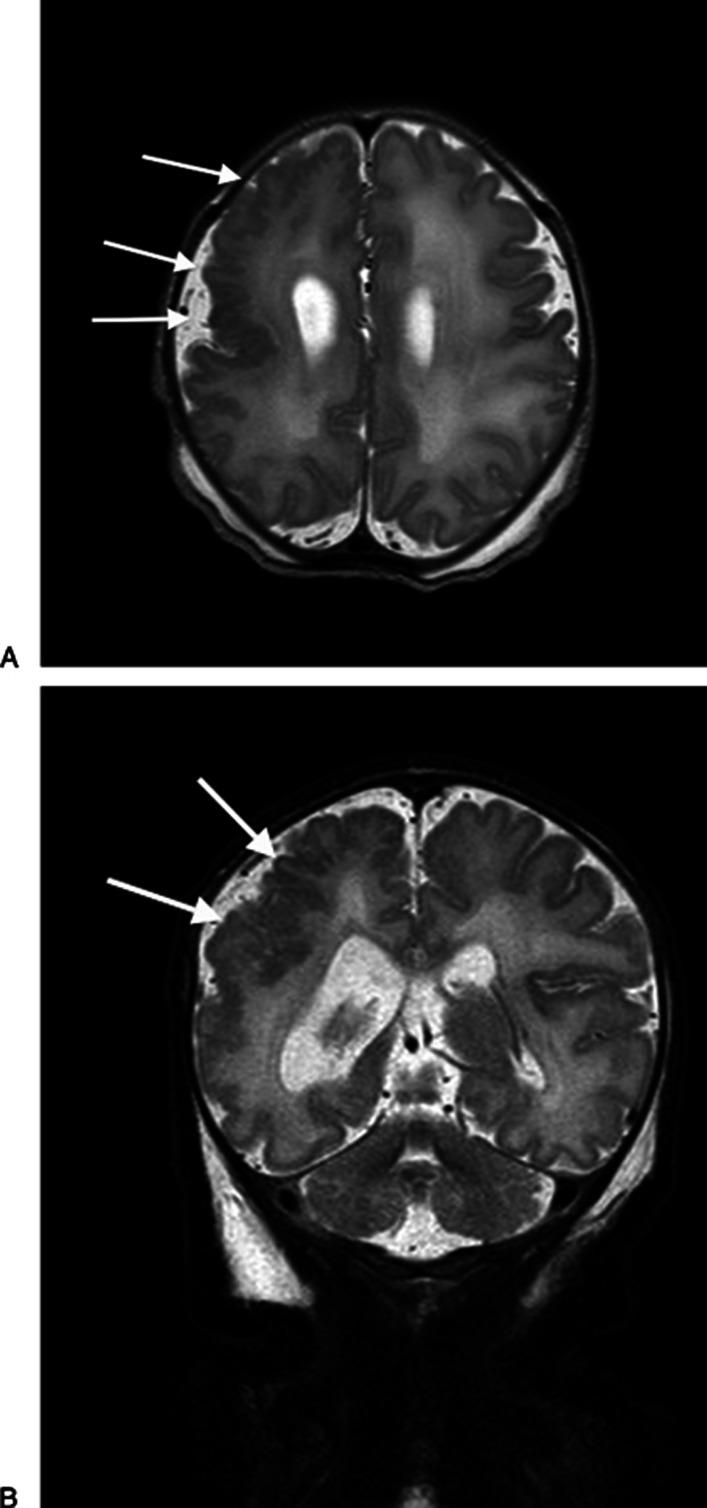

多小脑回畸形与先天性细小病毒B19感染。

Polymicrogyria and congenital parvovirus b19 infection.

Fetal parvovirus B19 infection causes anemia, hydrops, and pregnancy loss but is generally not considered teratogenic. Nevertheless, disturbances of neuronal migration have been described with congenital parvovirus infection. We evaluated a term infant with congenital parvovirus disease and polymicrogyria. We compared this case with four other reports of central nervous system disease after birth to parvovirus-infected mothers. After an extensive diagnostic evaluation, this infant was found to have congenital parvovirus disease with severe anemia and nonimmune hydrops as well as extensive polymicrogyria. Although rare, this report and literature review suggest that parvovirus B19 has the potential to disrupt normal neurodevelopment. We suggest that infants with severe congenital parvovirus infection have close developmental surveillance and if symptomatic undergo neuroimaging to assess for disorders of neuromigration.

摘要

胎儿细小病毒B19感染可导致贫血、水肿和流产,但一般不被认为具有致畸性。然而,已有先天性细小病毒感染导致神经元迁移障碍的相关描述。我们评估了一名患有先天性细小病毒病和多小脑回畸形的足月儿。我们将该病例与另外四例母亲感染细小病毒后出生的中枢神经系统疾病报告进行了比较。经过广泛的诊断评估,发现这名婴儿患有先天性细小病毒病,伴有严重贫血和非免疫性水肿以及广泛的多小脑回畸形。尽管罕见,但本报告及文献综述表明,细小病毒B19有可能扰乱正常的神经发育。我们建议,患有严重先天性细小病毒感染的婴儿应进行密切的发育监测,如有症状应进行神经影像学检查以评估神经元迁移障碍。